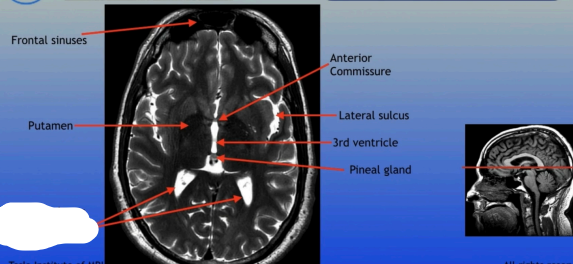

Frontal Sinus

Posterior Horn of Lateral Ventricle

Frontal Sinuses

Putamen

Posterior Horns of the Lateral Ventricles

Anterior Commissure